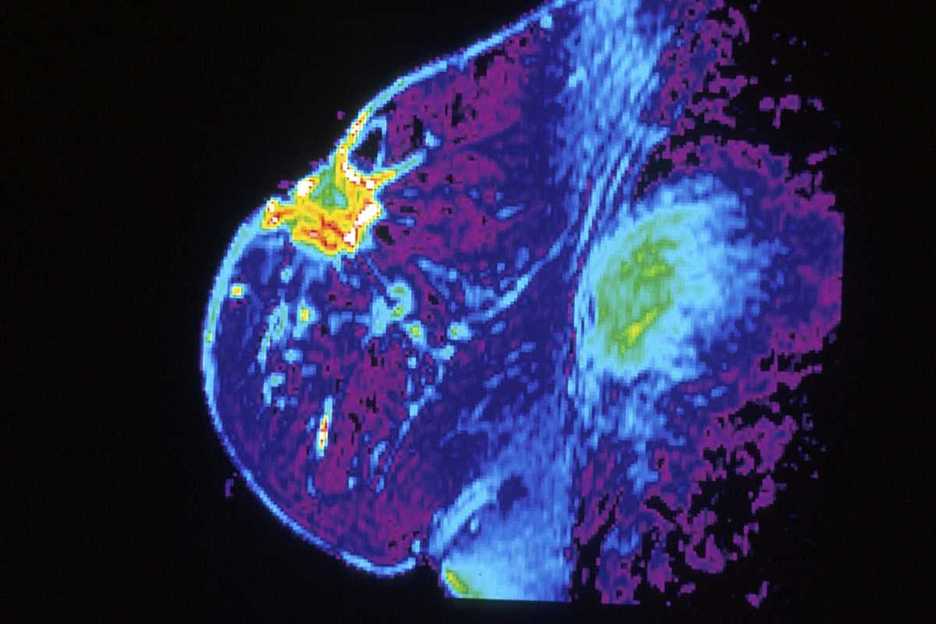

Un estudio de los servicios de Oncología Radioterápica de los centros Instituto Catalán de Oncología (ICO) demuestra que la irradiación parcial de mama ofrece mejores resultados y disminuye la toxicidad. El estudio se basa en la evaluación de 289 pacientes que han sido sometidas a la irradiación parcial de mama en el período de 2004 a 2017.

Esta técnica consiste en irradiar exclusivamente la región donde se encuentra el tumor y la zona de recaída potencial, por lo que se reduce el volumen de tratamiento y, consecuentemente, los efectos secundarios.

El principal objetivo de este estudio consiste en describir la experiencia de la Unidad de Braquiterapia del Servicio de Oncología Radioterápica del ICO en el campo de la irradiación parcial de mama a través de la braquiterapia multicáter (MC-BT).